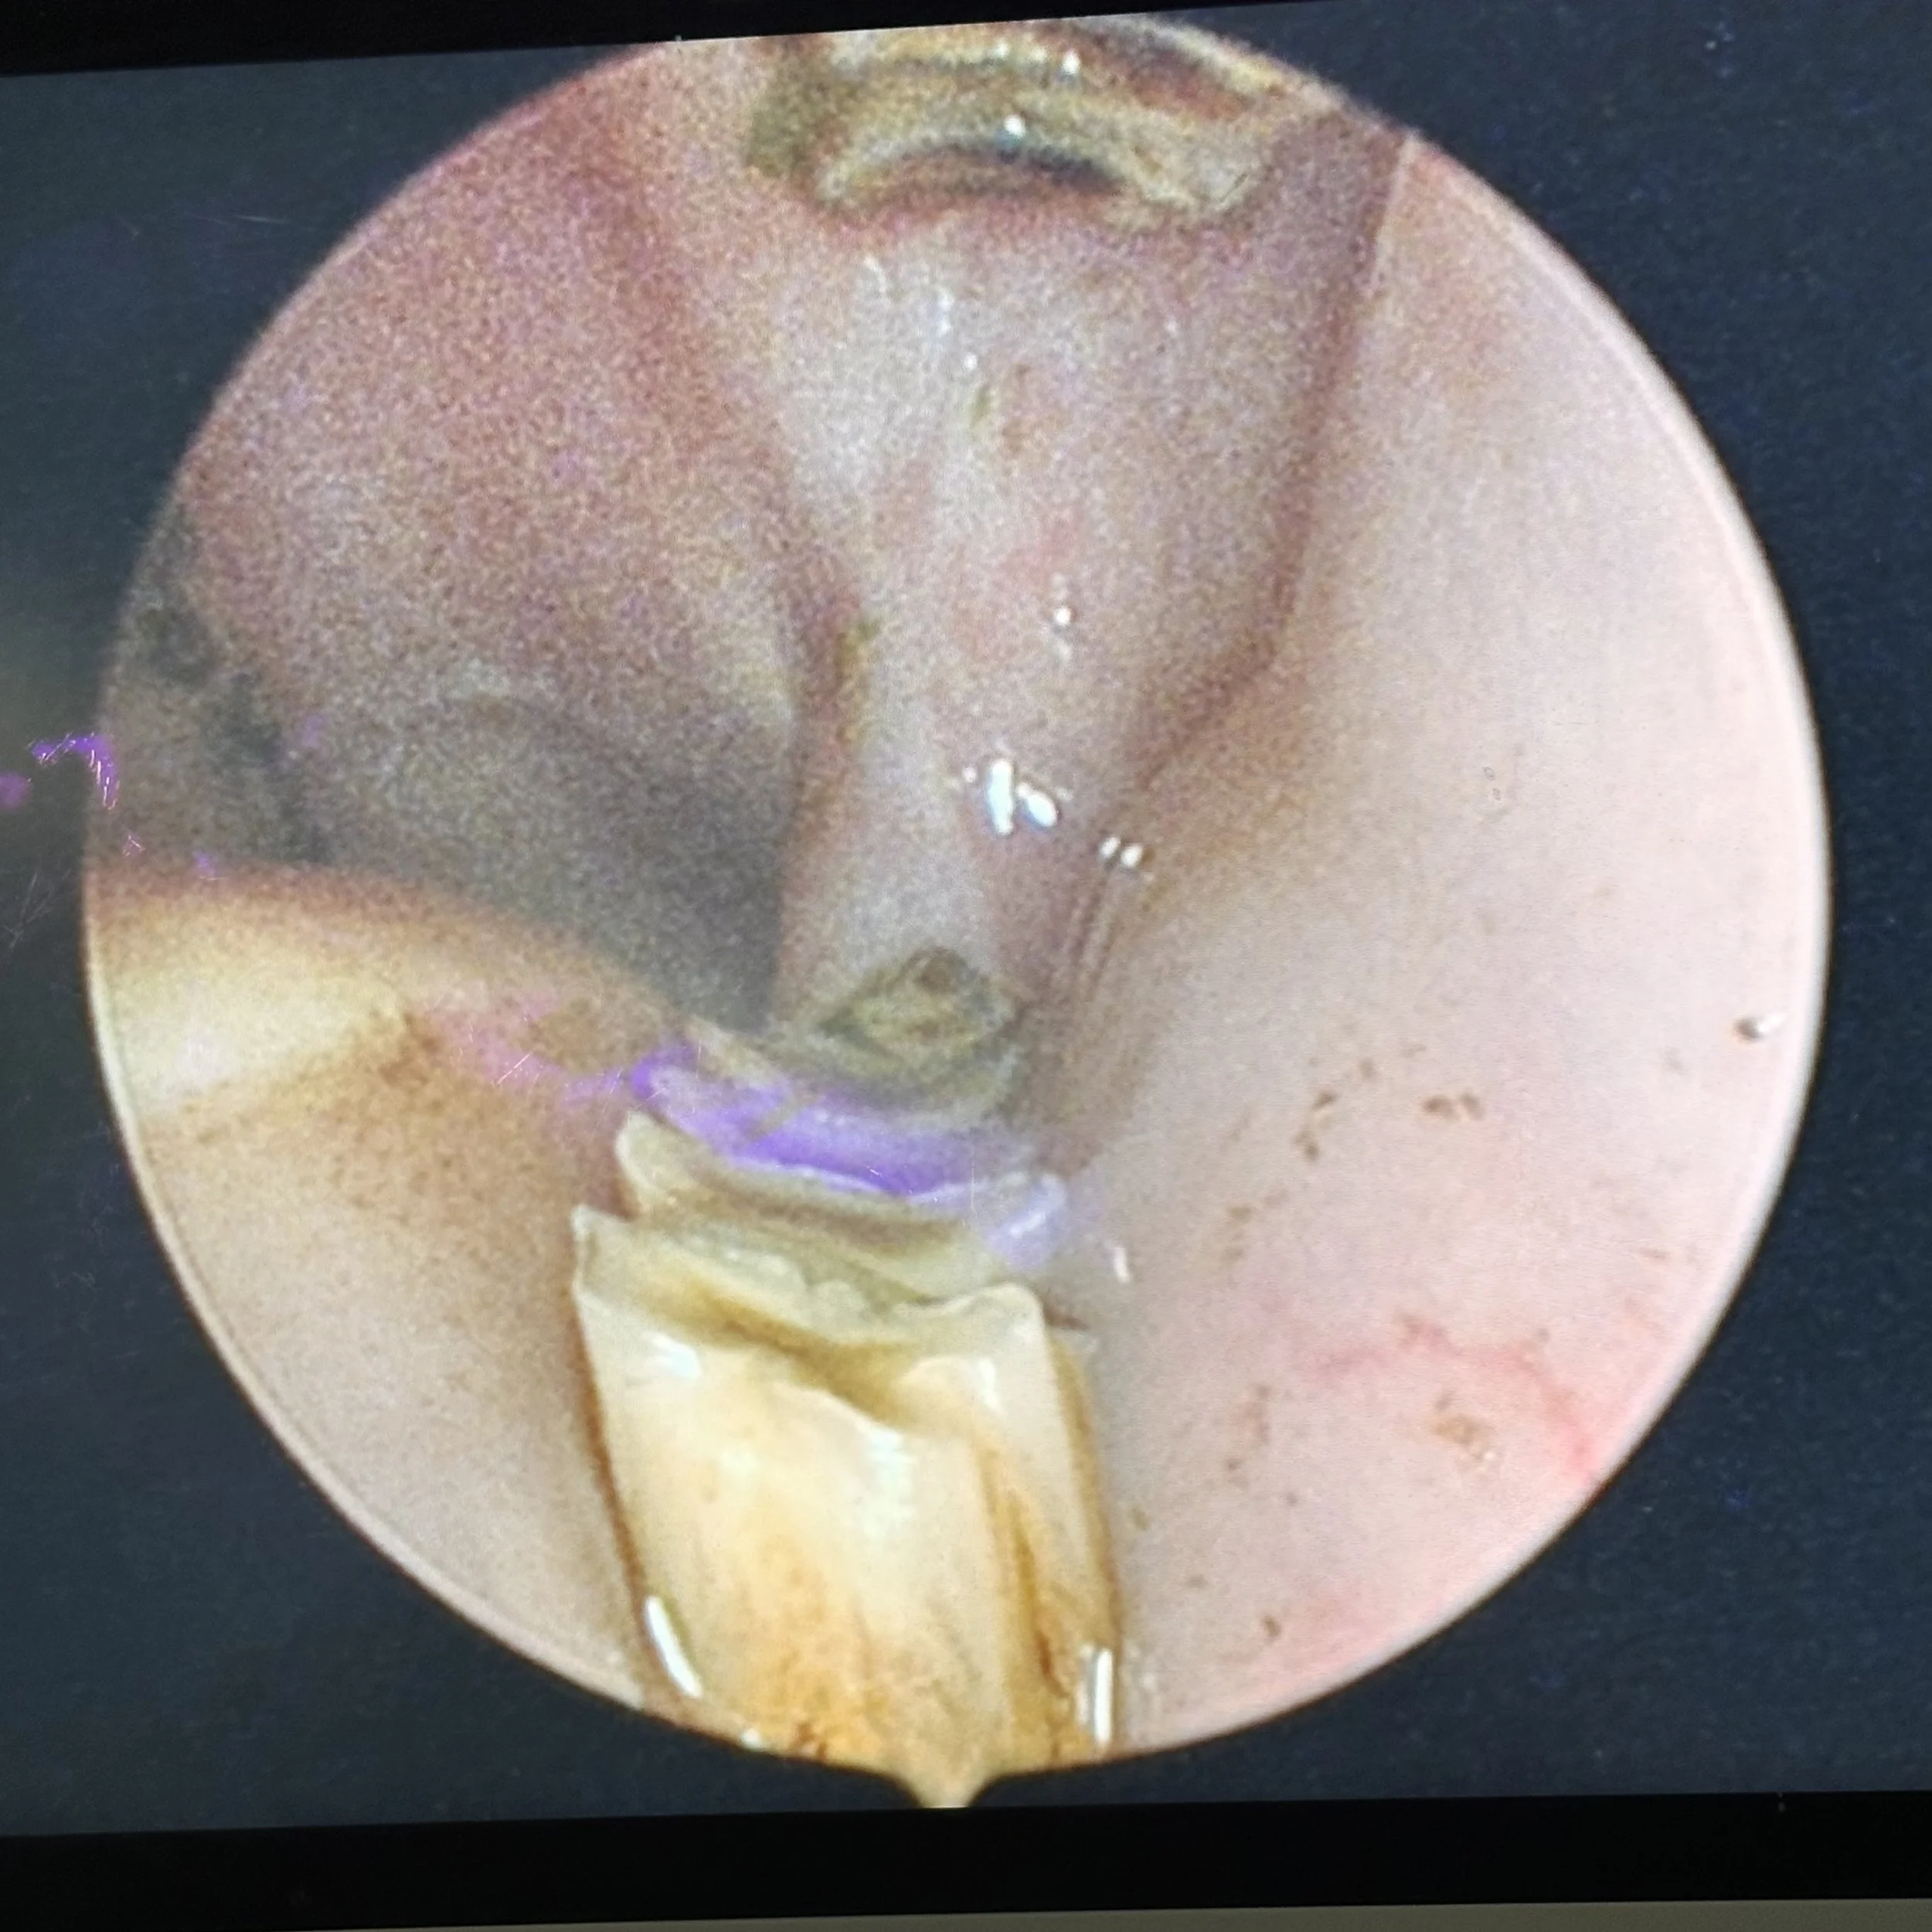

These photos show spurs on the rear molars. Having your rabbit’s teeth - including the back teeth, checked yearly is essential.